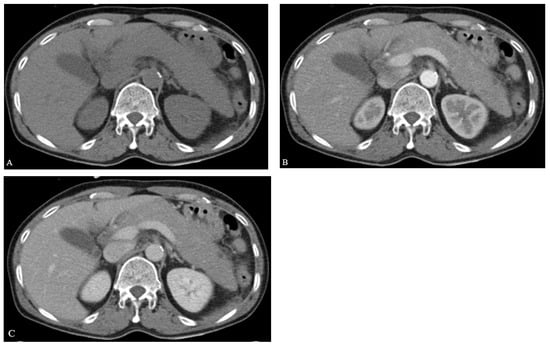

Therefore, he was given a final diagnosis of acute pancreatitis due to diffuse pancreas metastasis of ENKTL, and we resumed chemotherapy using the SMILE regimen. On the second day after fasting, epigastric pain and tenderness started to improve, and the patient resumed oral food consumption. In the follow-up CT performed after 2 months, pancreas enlargement was improved (Figure 5). The patient continued with his chemotherapy with the SMILE regimen, but refused to continue after the third cycle due to severe generalized weakness, and eventually died due to pneumonia. Figure 6 summarized our patient’s hospital course with timeline.

Figure 5.

CT finding after 2 months. Pancreatitis is improved and no complication is observed.